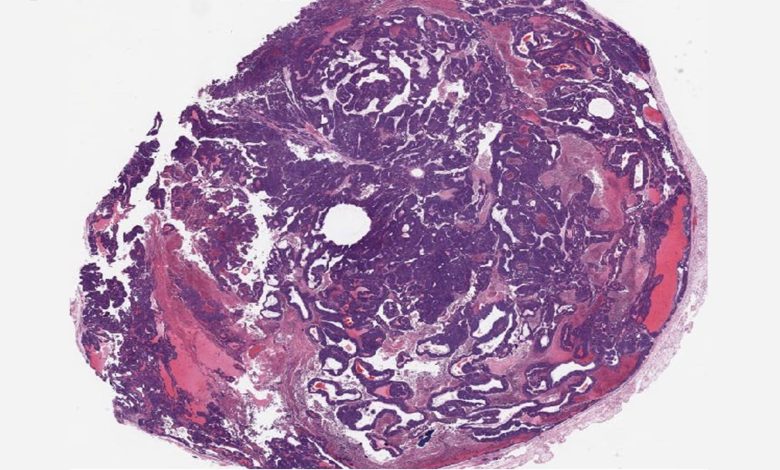

Um tumor mamário de um camundongo knockout para BPTF; animais com níveis mais baixos desta proteína tiveram menos metástases de câncer e viveram mais do que aqueles com níveis normais de BPTF. Crédito: laboratório dos Santos/CSHL

Uma pesquisa do laboratório da professora associada Camila dos Santos do CSHL mostra que a inibição da proteína BPTF em camundongos pode retardar a metástase do câncer ER+ e restaurar a suscetibilidade dos tumores à terapia hormonal. O estudo está publicado na revista Comunicações da Natureza.